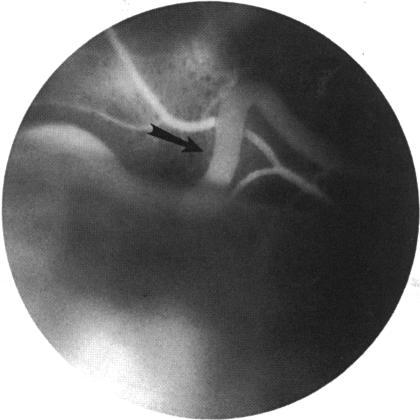

Sturge-Weber syndrome is a disorder characterized by ipsilateral cavernous hemangioma of the face, uvea, and brain in patients who may present with an enlarged eye, exudative retinal detachment, glaucoma, and seizures. This report presents the clinicopathologic findings of an otherwise healthy infant with ipsilateral arteriovenous and capillary hemangiomas of the face and uveal tract, microphthalmos, iris heterochromia, hypotony, and absence of central nervous system involvement. The association of an arteriovenous-capillary angioma of the ocular adnexa and ipsilateral uveal tract is a syndrome that is distinct from Sturge-Weber syndrome.

斯特奇-韦伯综合征是一种疾病,其特征为面部、葡萄膜和脑部同侧出现海绵状血管瘤,患者可能表现为眼球增大、渗出性视网膜脱离、青光眼和癫痫发作。本报告展示了一名原本健康的婴儿的临床病理结果,该婴儿面部和葡萄膜道存在同侧动静脉和毛细血管血管瘤、小眼球、虹膜异色、低眼压,且无中枢神经系统受累。眼附属器和同侧葡萄膜道的动静脉-毛细血管血管瘤的关联是一种与斯特奇-韦伯综合征不同的综合征。